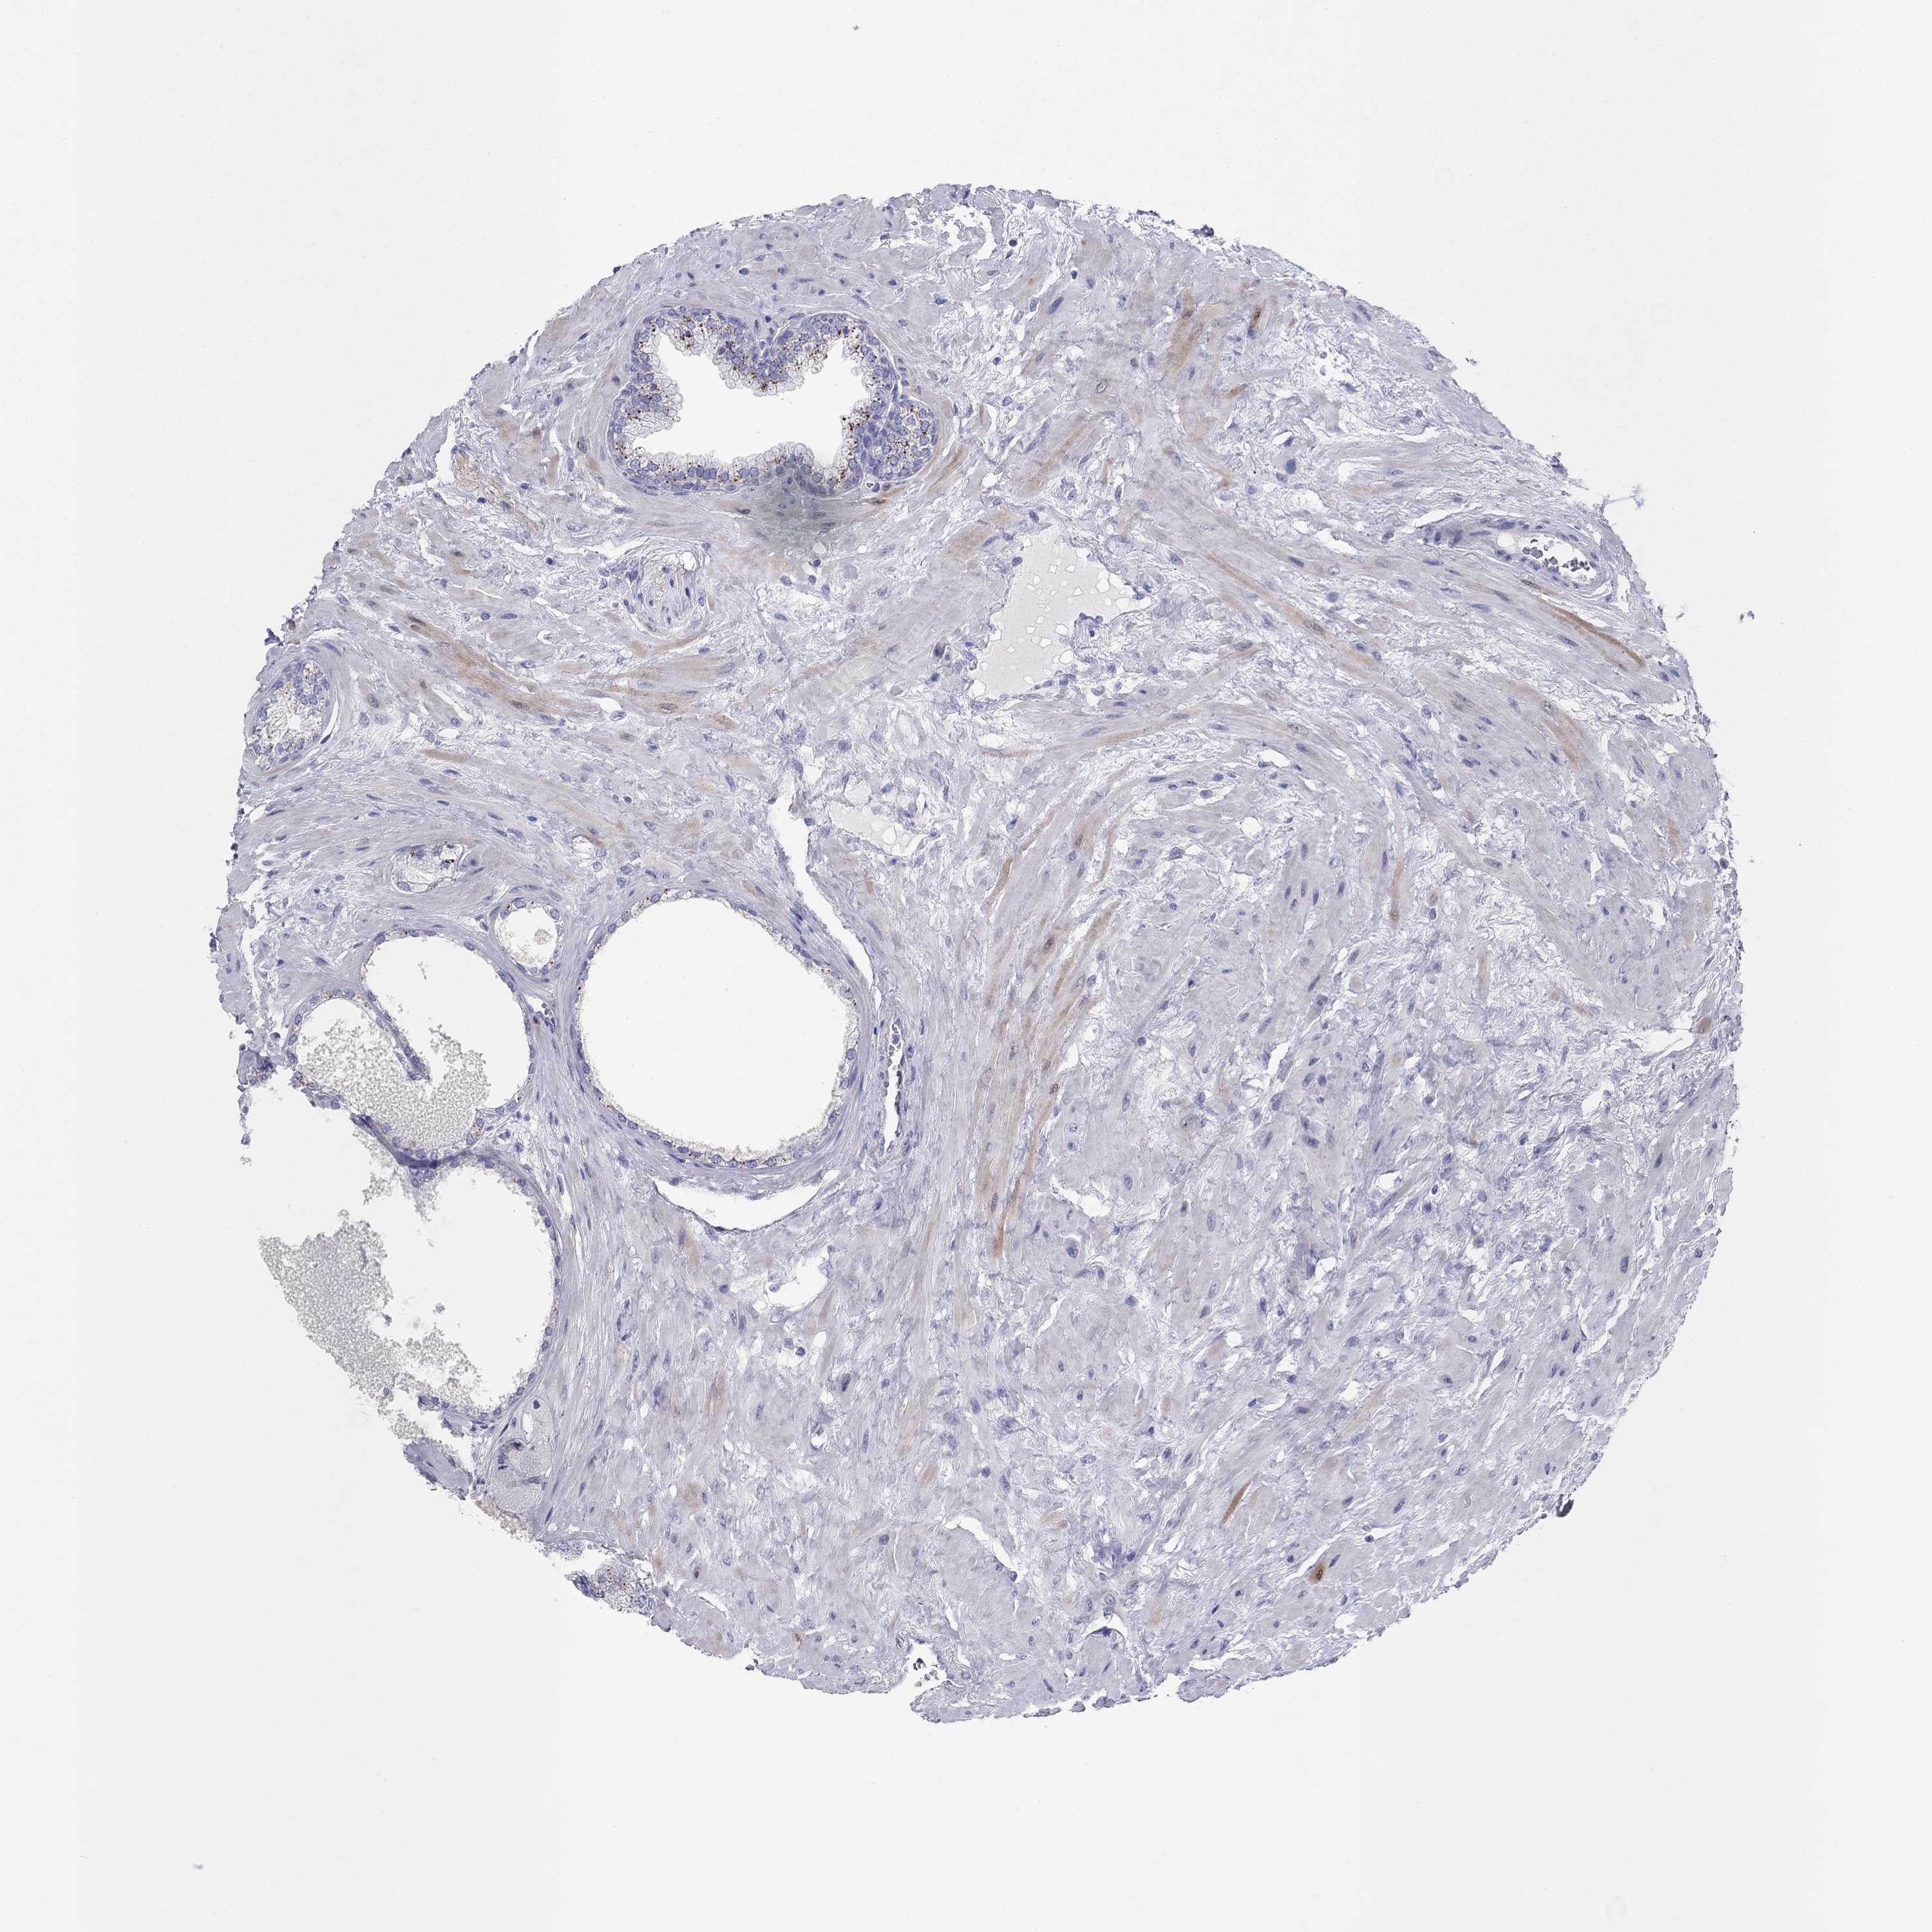

PROSTATE CANCER - Protein expressioni

A mouse-over function shows sample information and annotation data. Click on an image to view it in a full screen mode. Samples can be filtered based on level of antibody staining by selecting one or several of the following categories: high, medium, low and not detected. The assay and annotation is described here.

Antibody stainingi

Antibody staining in the annotated cell types in the current human tissue is reported as not detected, low, medium, or high, based on conventional immunohistochemistry profiling in selected tissues. This score is based on the combination of the staining intensity and fraction of stained cells.

Each image is clickable and will lead to virtual microscopy that enables deeper exploration of all samples and also displays staining intensity scores, fraction scores and subcellular localization as well as patient and tissue information for each sample.

Antibody HPA031636

Antibody HPA076665

Staining

High

Medium

Low

Not detected

Intensity

Strong

Moderate

Weak

Negative

Quantity

>75%

75%-25%

<25%

None

Location

Nuclear

Cytoplasmic/membranous

Cytoplasmic/membranous,nuclear

Adenocarcinoma, Low grade

Adenocarcinoma, NOS

Adenocarcinoma, Medium grade

Adenocarcinoma, High grade